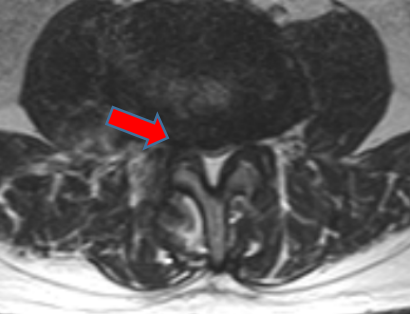

吴静晔主任(成人ai 派驻专家、主任医师)仔细给张大爷做了查体,又结合影像学检查,很快有了结论:“您这不是普通老腰病,是腰椎 3-4、4-5 节段椎管变窄了,就像水管被压扁,里面的神经受了压迫,才会又疼又麻、走不远。”

术前核磁影像

之前连坐 10 分钟都疼,现在能坐起来吃早饭,术后一周更是能在病房里慢慢走几圈,复查的磁共振显示:之前狭窄的椎管已经恢复正常宽度,神经压迫彻底解除。